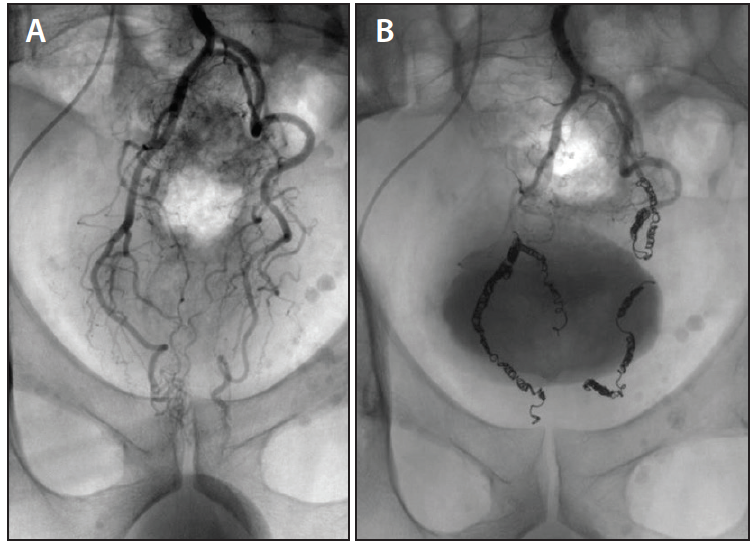

Figure 3 from Embolization of the hemorrhoidal arteries (the emborrhoid technique) a new Hemorrhoid Embolization Technique Technical success was defined as embolization of at least 1 branch of the sra or mra. Clinical success was defined as. The embolization of the rectal arteries to treat hemorrhoids requires a good understanding of. If you’re suffering from hemorrhoids and finding little relief from conventional treatments, hemorrhoid artery embolization might be the solution you need. The procedure takes 90. Hemorrhoid Embolization Technique.